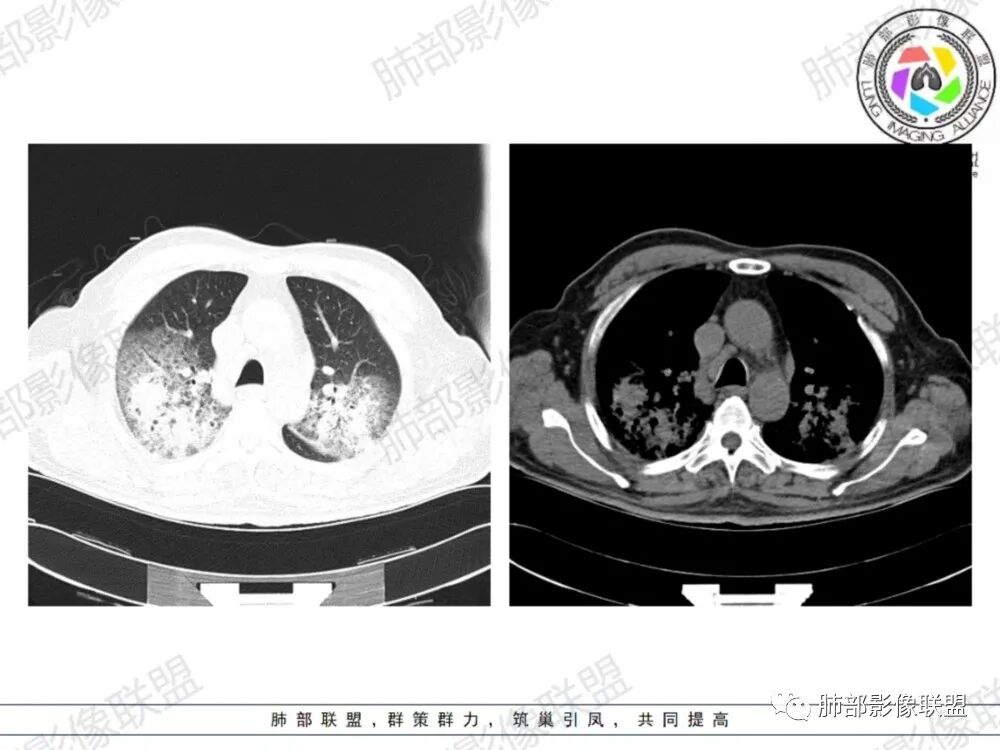

晨读:老年男性患者,咳嗽气喘3天入院,伴有发热,体温38.2℃,有糖尿病,高血压病史,有长期吸烟史,近期旅游史,白细胞,中性粒,CRP,PCT增高,肝功能损害,血气分析:低氧血症,胸部CT:双上肺及右下肺实变密度影伴周围磨玻璃密度影,边界整体清楚,内部支气管走形自然,伴双侧少量胸腔积液,综合考虑感染性病变,重症社区获得性肺炎,重点考虑非典型病原体,军团菌可能,鉴别肺克,结核合并感染

晨读老年患者,咳嗽气喘三天,腹泻,有多脏器的损害。有基础病的病史,糖尿病,高血压。旅游病史。两位靠后分布的大片状的实变影及磨玻璃样阴影,跨叶小叶性的分布,支气管充气征。内部的小叶间隔局部增厚。纵隔淋巴结不大,右侧胸腔积液。首先考虑感染性的病变,靠后重力感,肺克雷伯杆菌肺炎。鉴别诊断军团菌肺炎。

双肺多发斑片及大片状高密度影,周围伴磨玻璃影,界欠清晰,内见多发囊状透亮影呈蜂窝状,病变内支气管走形规则,无肺气肿背景,双侧胸腔积液,老年男性,糖尿病史,消化道症状,炎性指标升高,考虑军团菌感染,克雷白杆菌感染待排。

双肺大片磨玻璃影伴实变,边缘清晰,支气管通畅,磨玻璃影部分呈细网格状,胸膜下清晰,双侧胸腔积液,心影增大,心腔密度减低,贫血,考虑肺克,军团菌

胸部CT示双肺弥漫实变影伴周围磨玻璃影,跨叶段分布,可见小叶间隔增厚,支气管充气征,双侧胸腔积液。无明显坏死空洞及树芽征。

CT:双肺多叶段毛玻璃影、实变影、小叶内间质增粗,肺内病变有重力依赖趋势,双侧少量胸腔积液,无空洞、树丫;

军团菌感染可累及多个脏器,肺是主要的受侵器官。军团菌肺炎为广泛多叶分布的炎症。

1.病变复杂多样∶大片状实变影、斑片状模糊阴性,网格状阴性、小结节影。多叶受侵是本病重要影像学特征性改变。

3.呈小叶肺炎状改变,病变大小以肺小叶为单位的支气管肺炎,呈弥漫性的单或双侧分布。局部可融合呈高密度的团片状影像,本病又一典型的影像学特点。

4.病变常伴有胸水出现,肺部阴性多变的情况下伴有胸水形成应高度怀疑军团菌感染的可能。